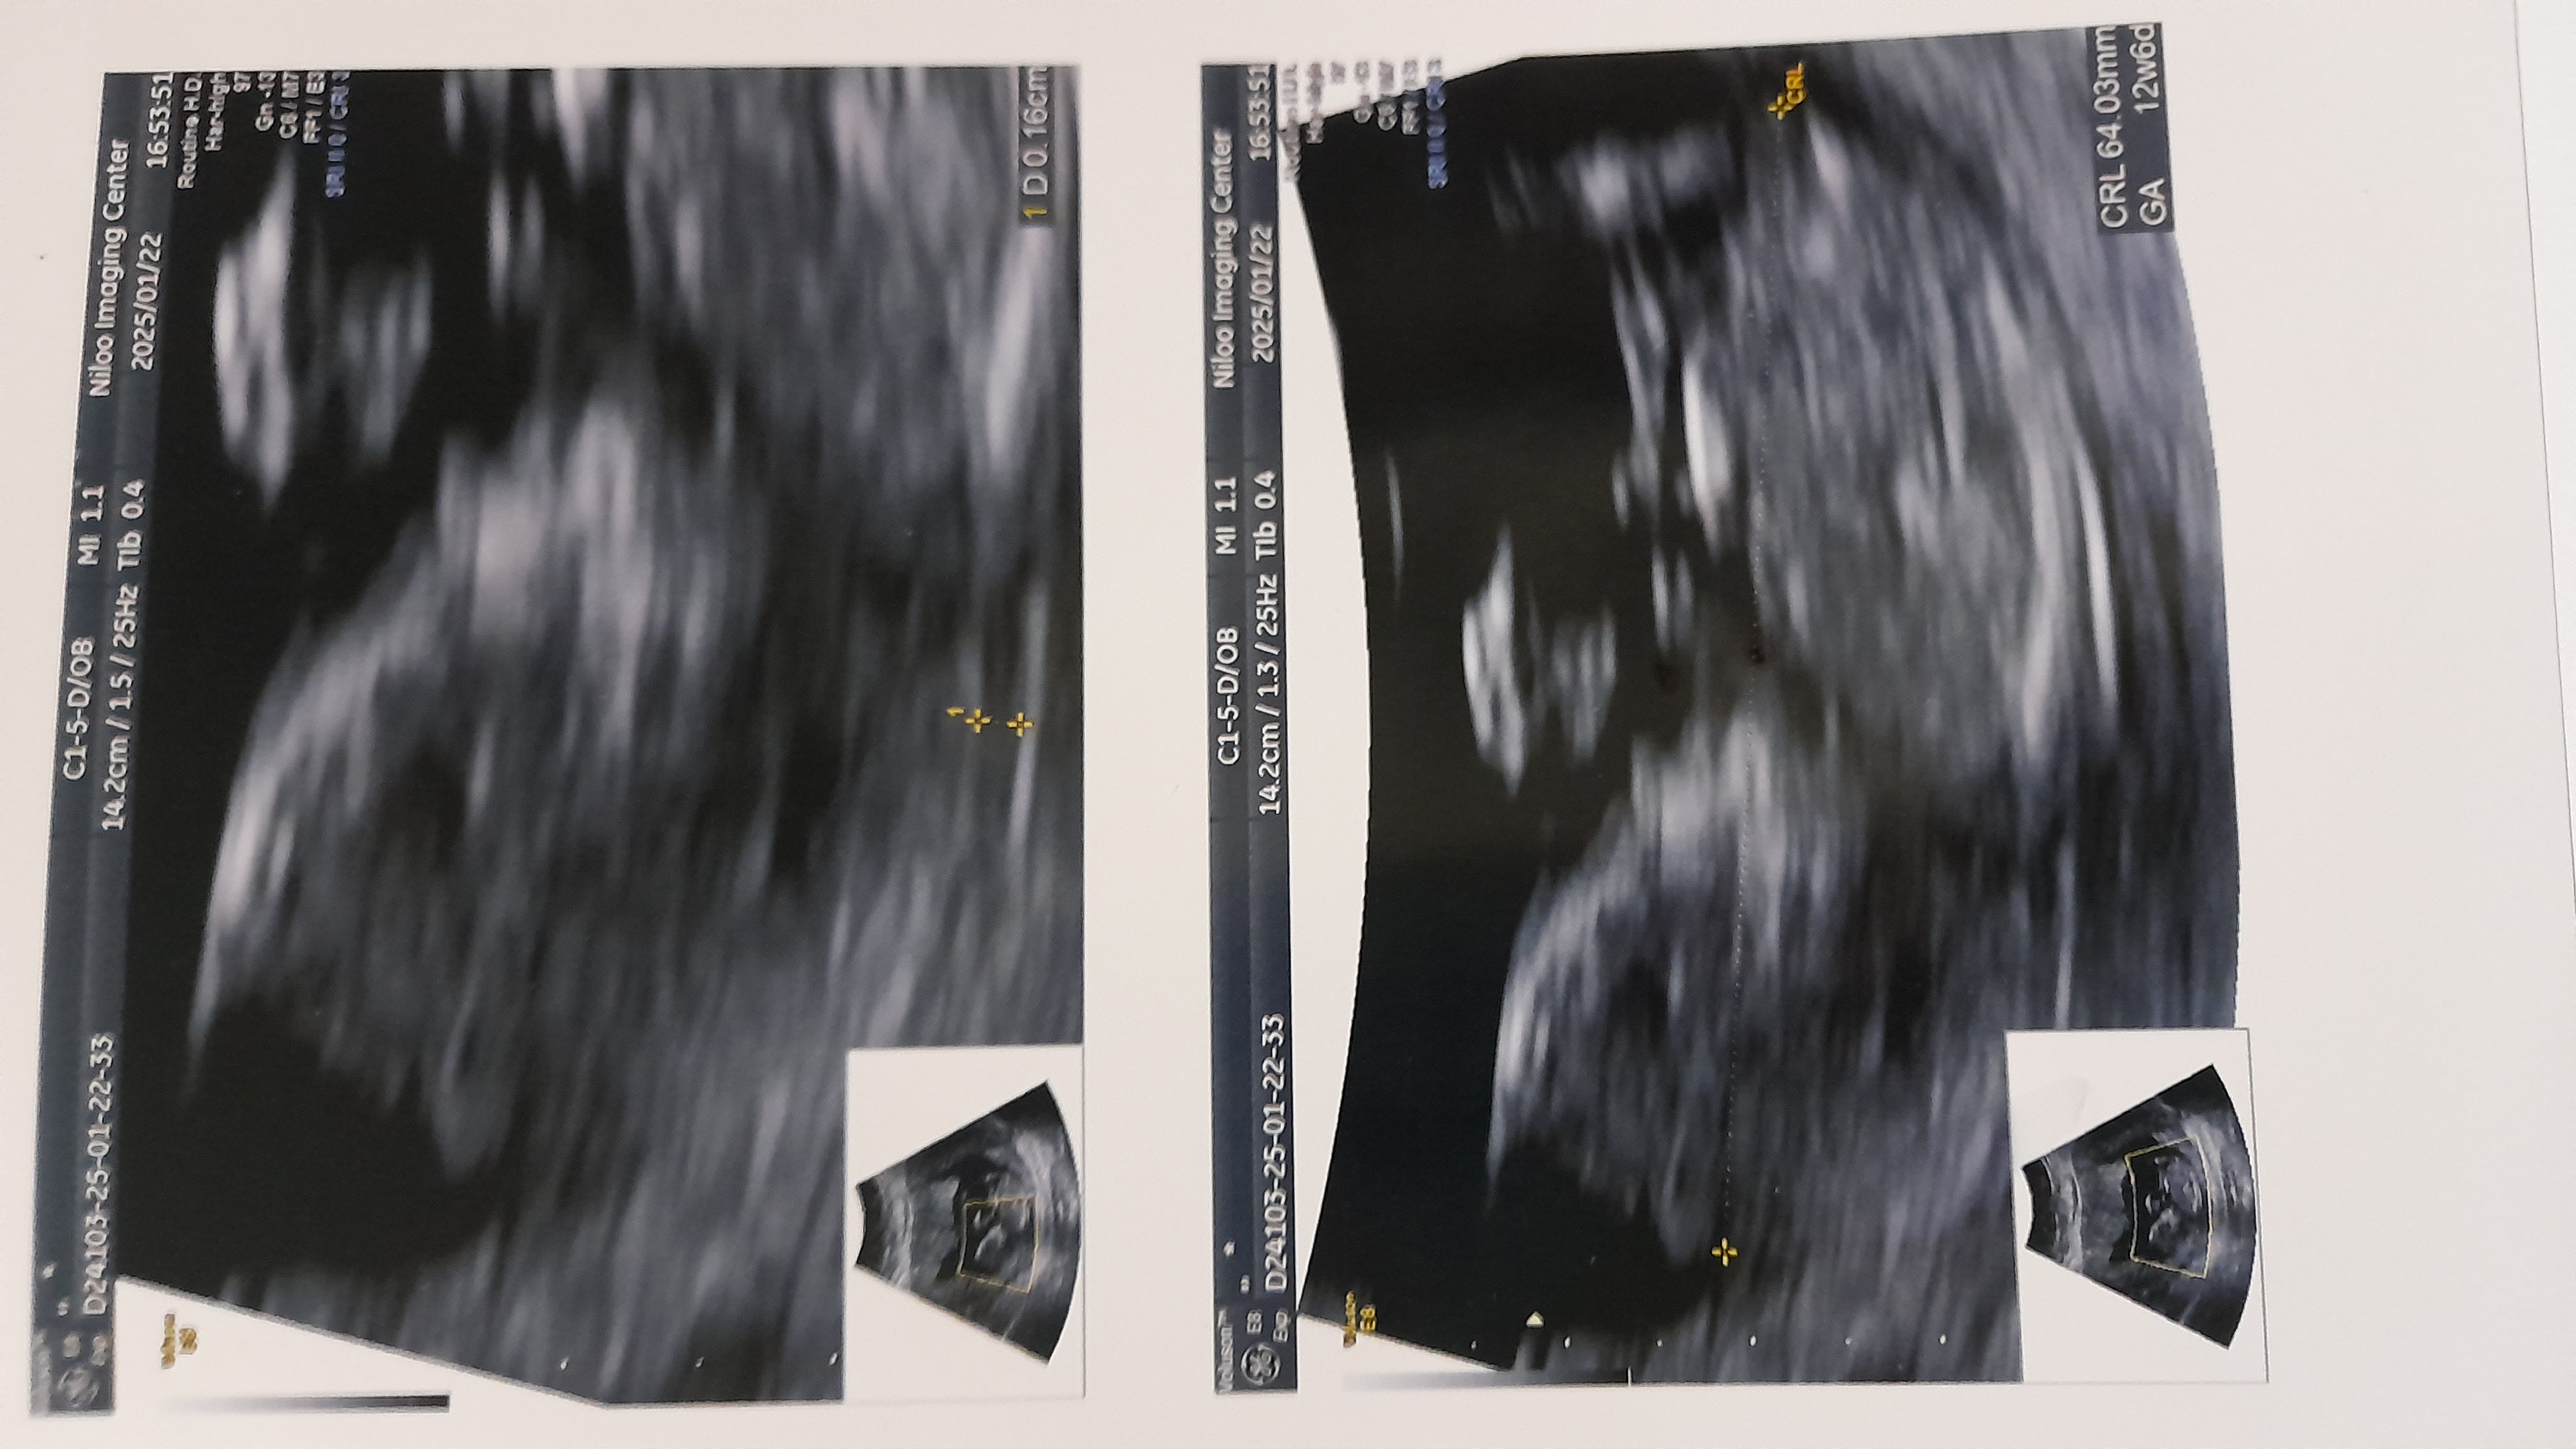

دختر نازم تو ۳۰ هفتگی پرکشیده لطفا برای دلم ی صلوات بفرستین منم براتون صلوات میفرستم ... انشاالله ک همیشه دل خوش باشین. ۱۶.۵.۱۴۰۳